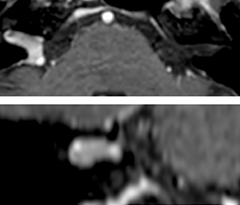

This is an example of acute ischemic stroke with distal occlusion of the right posterior cerebral artery. Note the improved visibility of the ischemic territory on the diffusion weighted image with high b-value. The 3D FLAIR shows a distal PCA occlusion. The fast SWIp depicts the thrombus on the isolated second echo image. The total scan time (including SmartBrain, preparations and a fast 3D T1w TSE Gd) is 8:00 minutes.